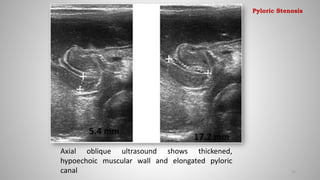

Axial oblique ultrasound shows thickened,

hypoechoic muscular wall and elongated pyloric

canal 25